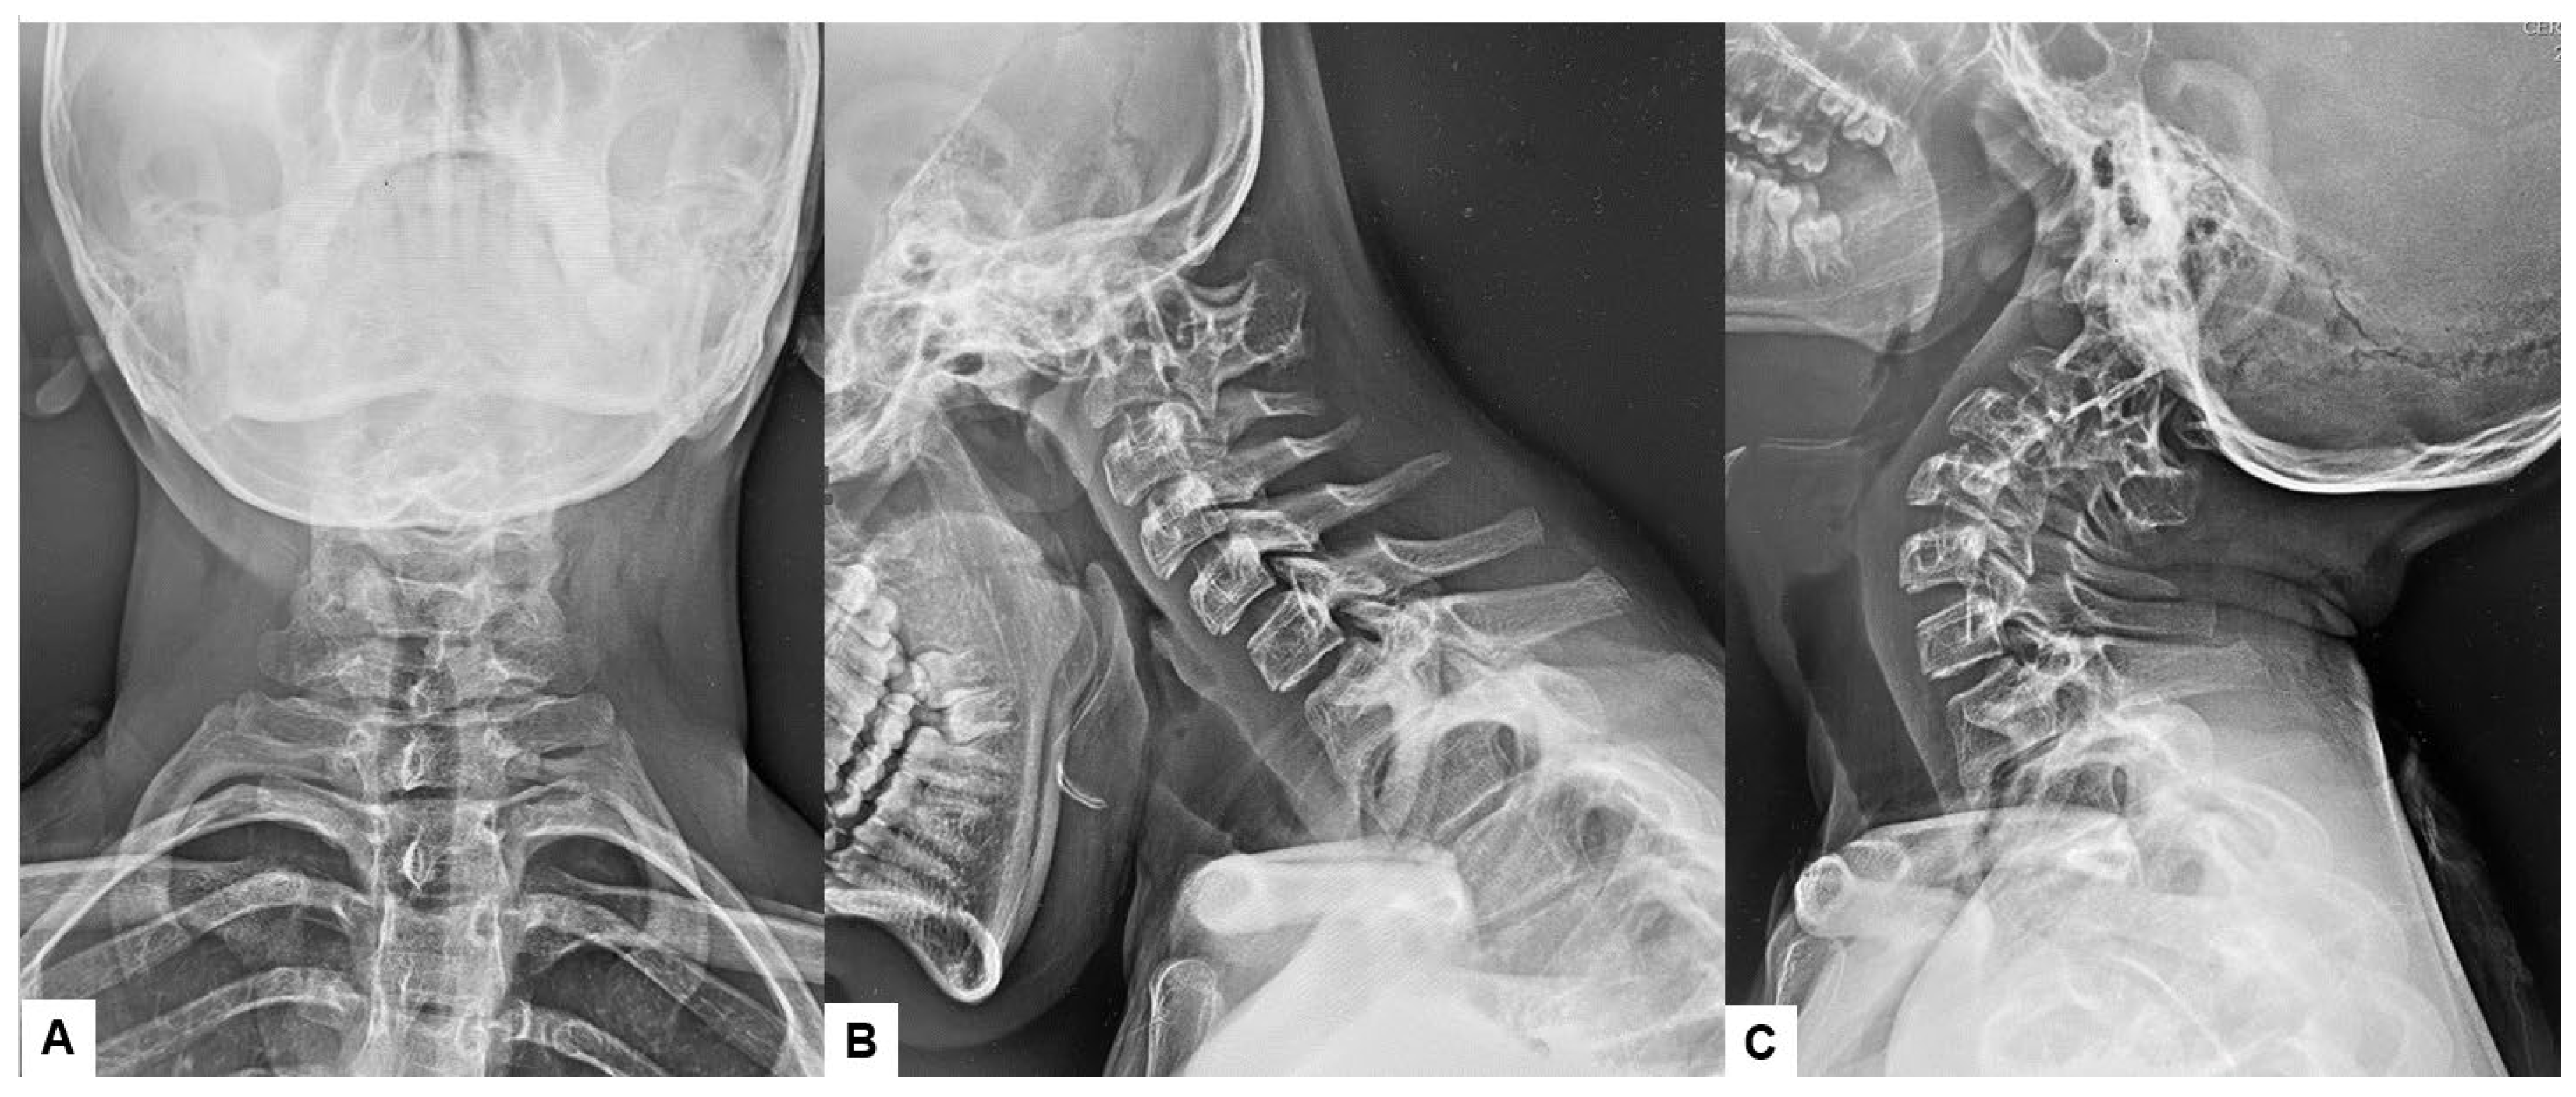

Preoperative cervical radiographs revealed a short neck and a C2/3 fusion anomaly. Dens protrusion into the foramen magnum measured 9.4 mm above McGregor’s line and 4.2 mm above McRae’s line, with an anteroposterior (AP) diameter of the foramen magnum measuring 10.7 mm (Figure 2). Preoperative magnetic resonance imaging (MRI) depicted severe compression of the cervicomedullary cord by the dens, with a cervicomedullary angle (CMA) measuring 116 degrees (Figure 3).

Figure 2.

Preoperative radiograms, (A) Antero-posterior radiogram, (B) Lateral flexion radiogram, (C) Lateral extension radiogram. (B,C) show a C2/3 fusion anomaly. A dens protrusion into the foramen magnum measured 9.4 mm above McGregor’s line and 4.2 mm above McRae’s line.